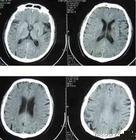

腦腔梗在臨床上較為常見,就是通常所說的腔隙性腦梗塞,屬於腦梗塞(腦血栓、腦栓塞、腔隙性腦梗塞、多發性腦梗塞、短暫性腦缺血發作)的一種特殊類型,多發生在基底節區。是在高血壓、動脈梗化的基礎上,腦深部的微小動脈發生閉塞,引起腦組織缺血性軟化病變。其病變範圍一般為2-20毫米,其中以2-4毫米者最為多見。臨床上患者多無明顯症狀,約有3/4的患者無病灶性神經損害症狀,或僅有輕微注意力不集中、記憶力下降、輕度頭痛頭昏、眩暈、反應遲鈍等症狀。部分多發性腦腔梗,可影響腦功能,導致智力進行性衰退,最後導致腦血管性痴呆。該病的診斷主要為CT或MRI檢查,